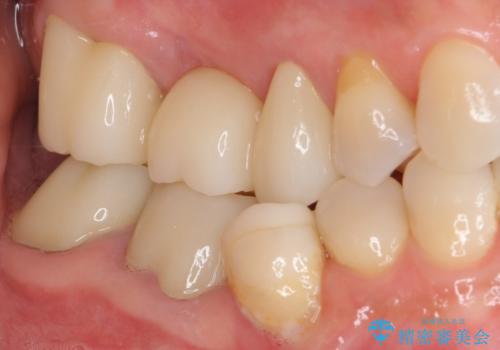

金属を全てセラミックに メタルフリー治療

土台に含まれている金属も含め、口腔内の金属は全て除去し、抜歯しなければならない歯は抜歯し、オールセラミッククラウンやセラミックインレーにて治療することとしました。

口の中を一切気にしなくて良くなり、患者様には大変満足していただきました。